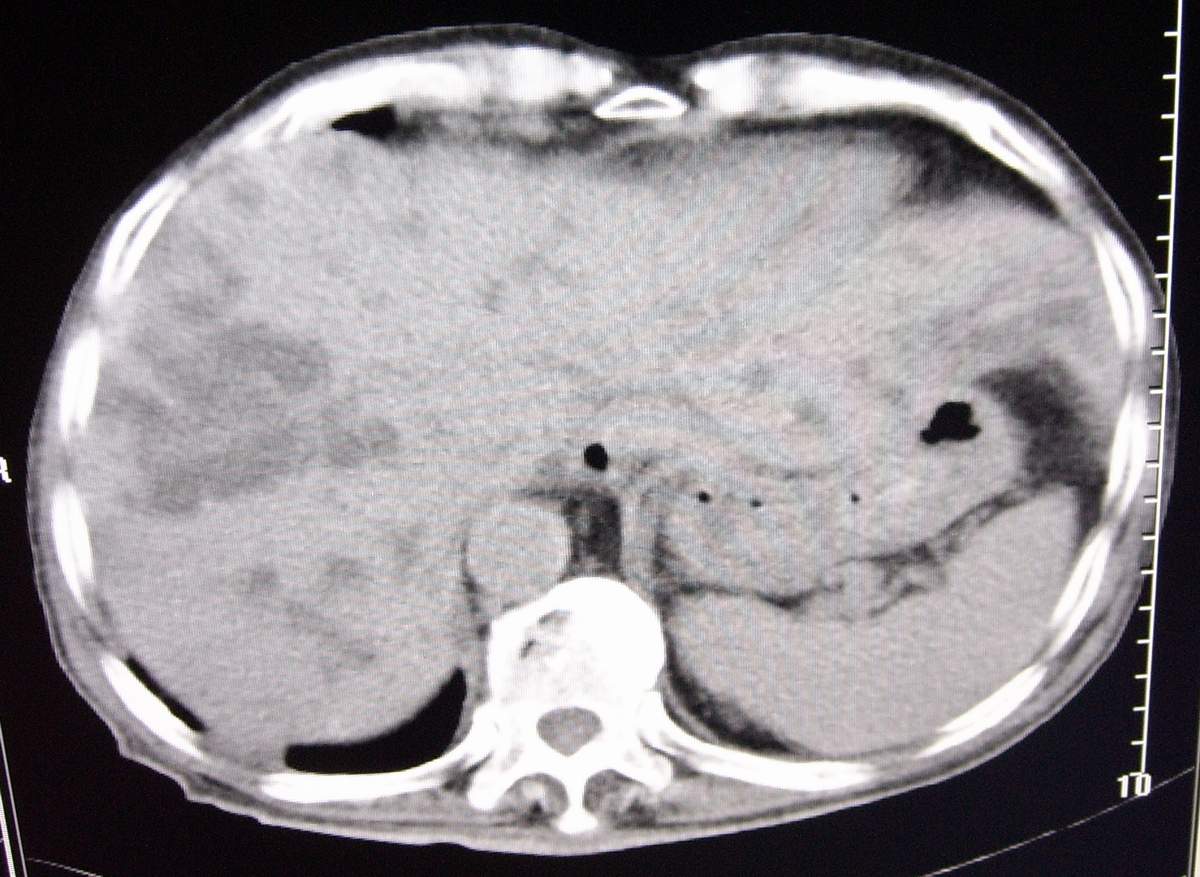

男,77岁,病史不详。

肝内胆管扩张、主胰管扩张 ,胰头影大,考虑胰头癌或胆管下端癌侵犯胰腺可能性大

另外见:胆囊结石 左肾囊肿

肝内外胆管明显扩张,但是程度较轻,应该是个慢性的过程,增强扫描后未见明显异常强化,胰管增宽、扩张考虑为胰头部占位性病变。

慢性胆囊炎,胆结石,左肾囊肿肝内胆管扩张,胰头大,考虑胰头癌

肝内外胆管明显扩张,肝门区见软组织密度肿块,胆囊壁增厚,胆囊扩大。胰头不大。考虑:肝门区胆管细胞癌。

考虑:1、华枝睾吸虫肝病(肝外胆管未见扩张,肝内胆管不成比例扩张,也就是失去分支规律的扩张,呈

外部呈柱状或囊状扩张,中部无明显扩张,而且边界不清);

2、胆囊结石、胆囊炎;

3、左肾小囊肿;

肝内胆管扩张明显,cbd未见明显扩张,胰管轻度扩张,肝门部胆总管癌?

肝内胆管普遍扩张,呈串珠状改变,走行不规则,且右叶胆管周围肝实质密度呈条片状减低,未见占位性病变,外周胆管及胰管扩张不及肝内胆管.胰腺钩突形态正常,胰十二指肠区域未见明显结节及肿块,初步考虑慢性胆管炎可能性大.请结合临床病史.另外用宽窗看一下吉氏筋膜有无增厚.

1肝门区域软组织影,肝内胆管明显扩张,胰管轻度扩张。考虑肝门区胆管细胞癌。2胆囊结石。3左肾小囊肿。

1 肝内外胆管扩张,肝内明显,胰管扩张,胰头明显增大,符合胰头癌双管征。2 胆囊壁略增厚,胆囊内可见高密度结石影,胆囊炎、胆结石3 左肾囊肿